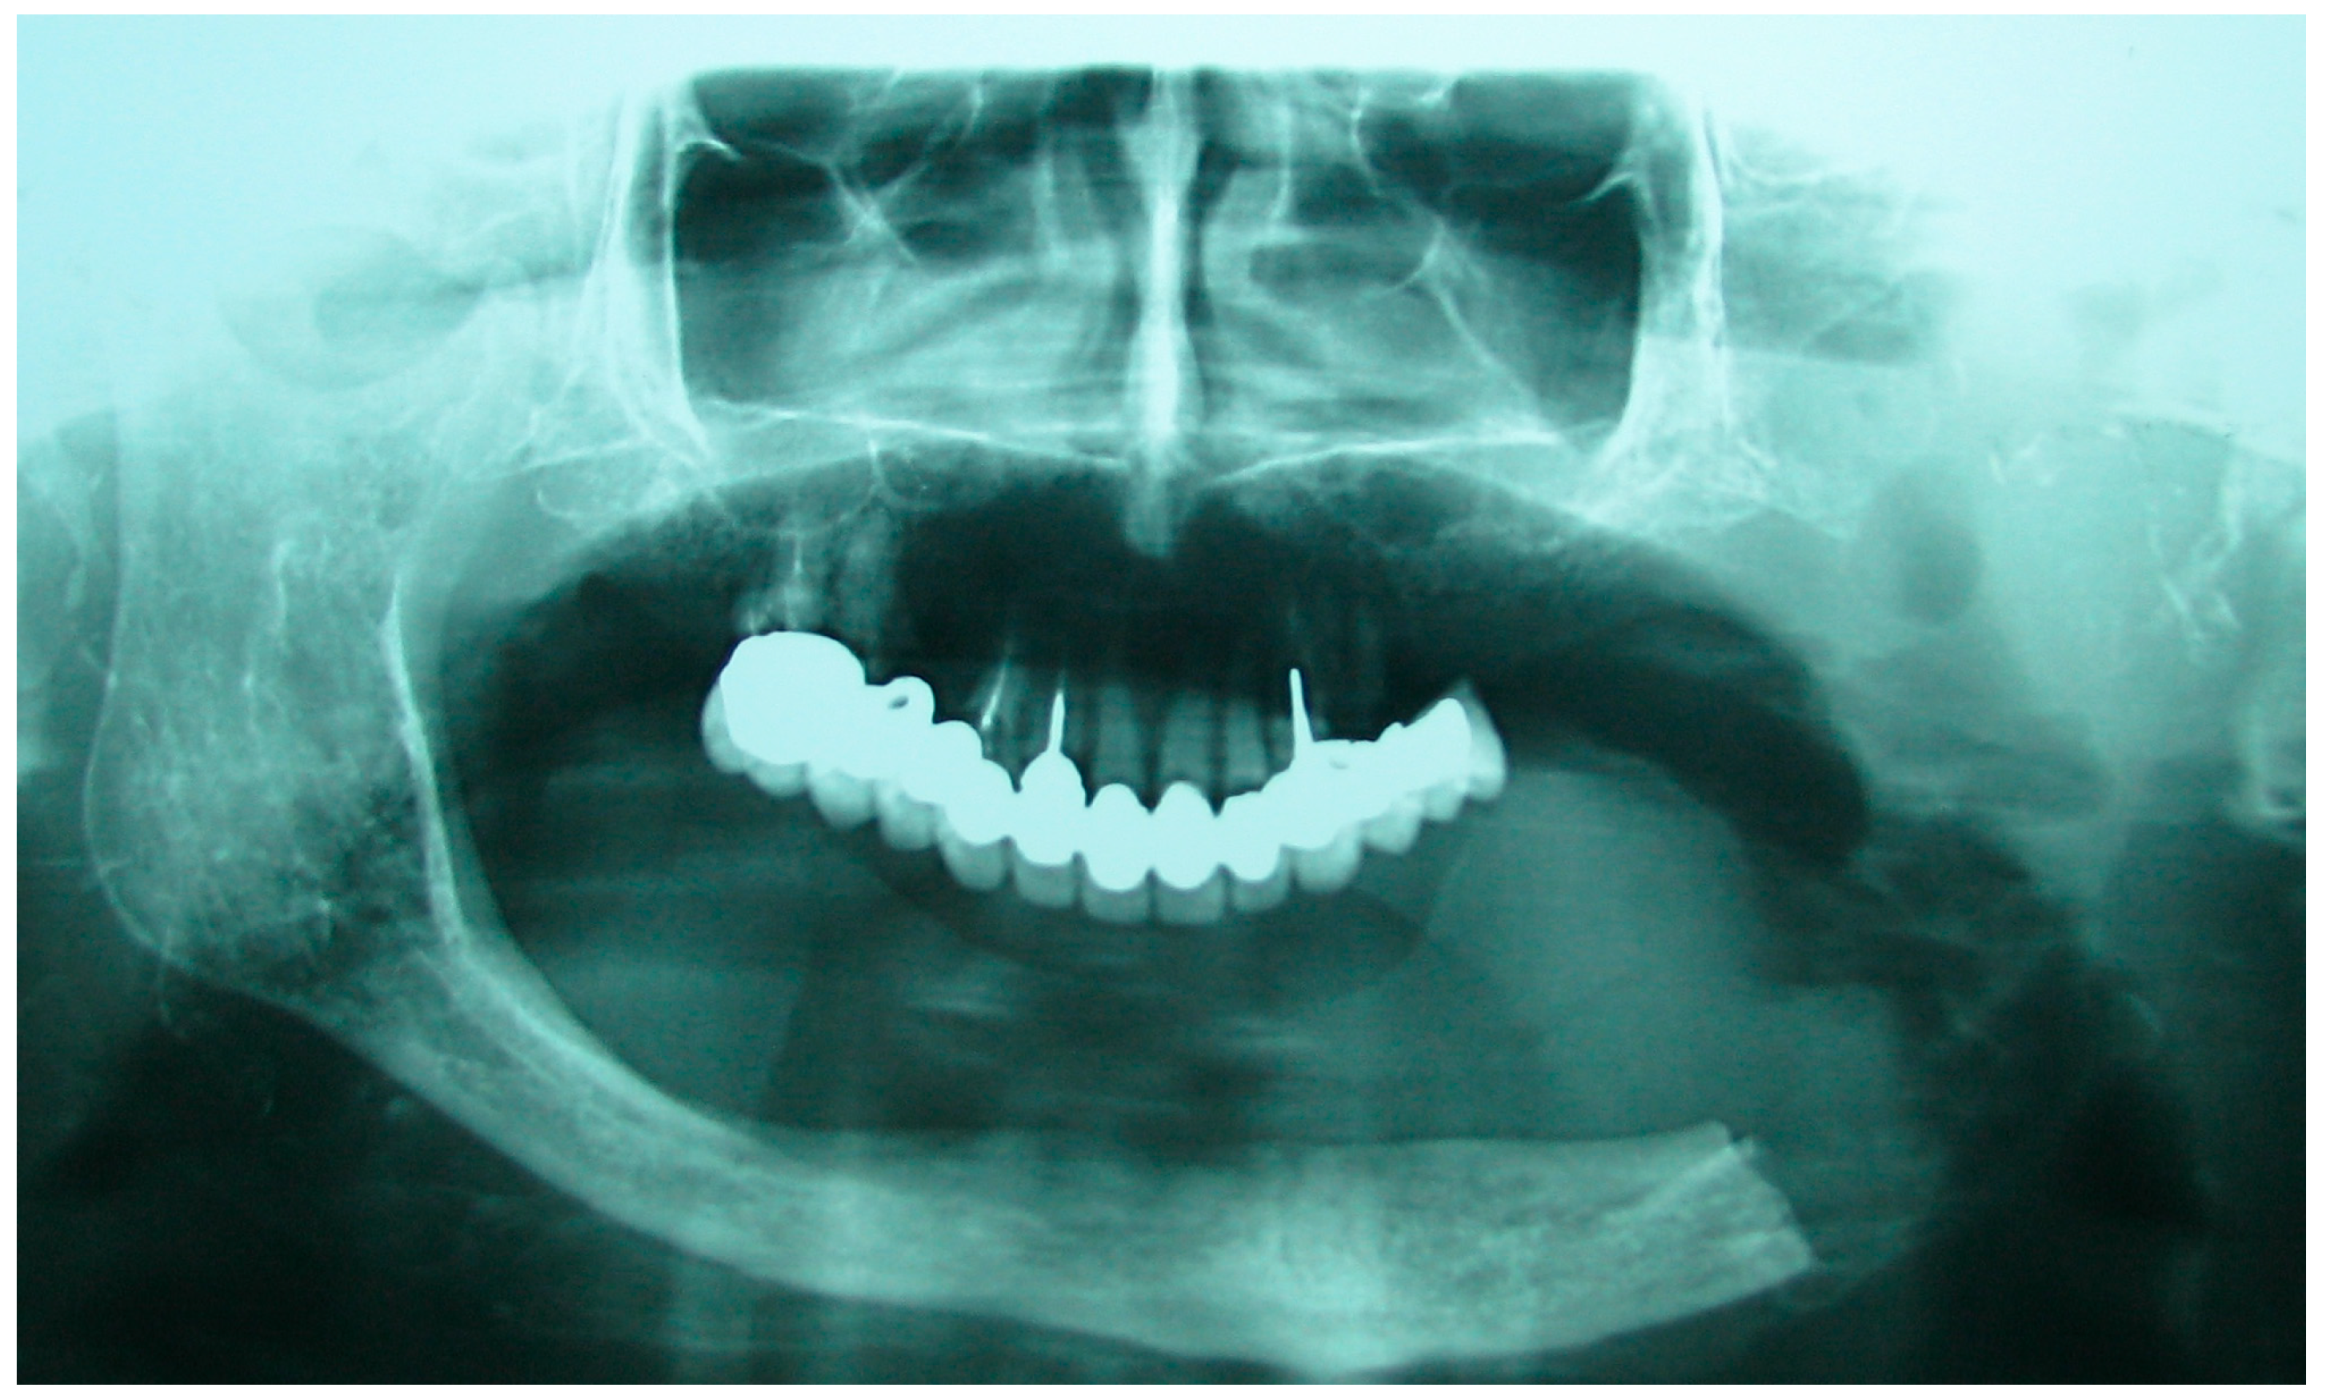

Figure 2. Patient with hemimandibulectomy L2 in orthopanoramic X-ray.

The patient in Case 1 had undergone surgery to remove a tumor that intersected the angle of the mandible. (L2) (Figure 1 and Figure 2). The upper elements were extracted soon after due to periodontal and endodontic issues. After being initially rehabilitated with a complete removable prosthesis (to regain function and aesthetic), two implants were subsequently placed in the 3.2 and 4.4 areas, and the final prosthesis was built in resin with a ball retention mechanism (Figure 3 and Figure 4).